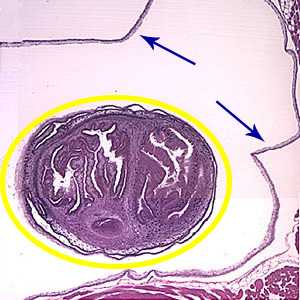

Larval Taenia solium.

Figure A: Larval Taenia solium cyst in a section of a lesion found in the right frontal lobe of a patient stained with hematoxylin and eosin (H&E), magnification 40×.

Figure B: An entire cysticercus seen within the bladder walls (blue arrows). A single scolex is visible inside yellow circle) within the cyst.

Figure C: Higher magnification (100×) of the cyst in Figures A and B. The parenchymatous portion of the cysticercus can be better observed.